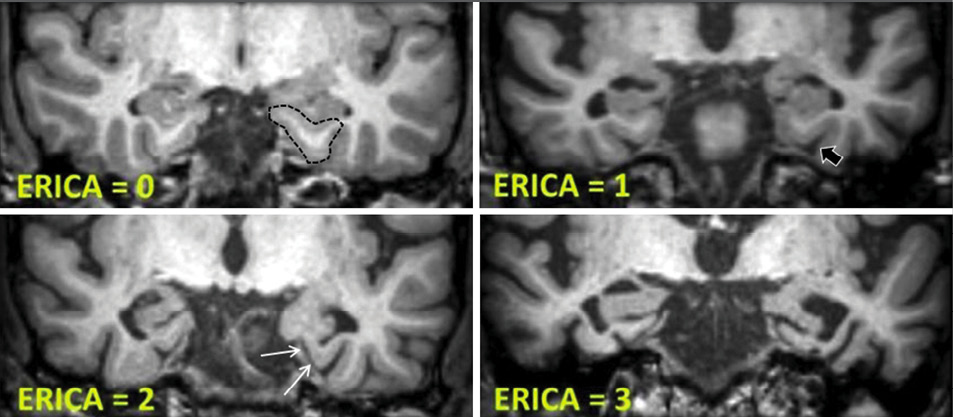

The ERICA score. The visual pattern for entorhinal cortex atrophy was defined as follows: A score of 0 indicated normal volume of the entorhinal cortex and parahippocampal gyrus (marked area); a score of 1, mild atrophy with widening of the collateral sulcus (black arrow); a score of 2, moderate atrophy with detachment of the entorhinal cortex from the cerebellar tentorium (the “tentorial cleft sign”; white arrows); and a score of 3, pronounced atrophy of the parahippocampal gyrus and a wide cleft between entorhinal cortex and the cerebellar tentorium. Enkirch, et al., Radiology 2018:288;1 © RSNA 2018.

In a modified tactic, researchers categorized ERICA in four stages based on the structural health of the entorhinal cortex. The scores were defined on a scale of zero to two with observed conditions ranging from normal volume of the entorhinal cortex and the parahippocampal gyrus to pronounced atrophy of the parahippocampal gyrus and a wide cleft between the entorhinal cortex and the cerebellar tentorium.

“During the initial development of the score, we were surprised to see recurring patterns of ERICA in patients with AD, especially a detachment of the entorhinal cortex from the cerebellar tentorium, which we later termed the ‘tentorial cleft sign’,” Dr. Enkirch said.

Patients with AD had higher ERICA scores than those with SCD, according to results. An ERICA score of two or greater discriminated between AD and SCD better than the MTA score, researchers said.